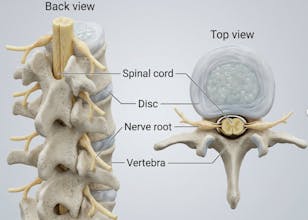

Natomy AI creates high-quality, medically accurate images and videos of human anatomy. Start with image-to-image: upload any low-quality photo, real image, or animation, and Natomy transforms it into an ultra-realistic anatomical visual. Unlike other AI tools that get anatomy wrong, Natomy is accurate every time—and fully editable by simply highlighting what you want changed and describing the update. Text-to-video launches in 2 weeks.